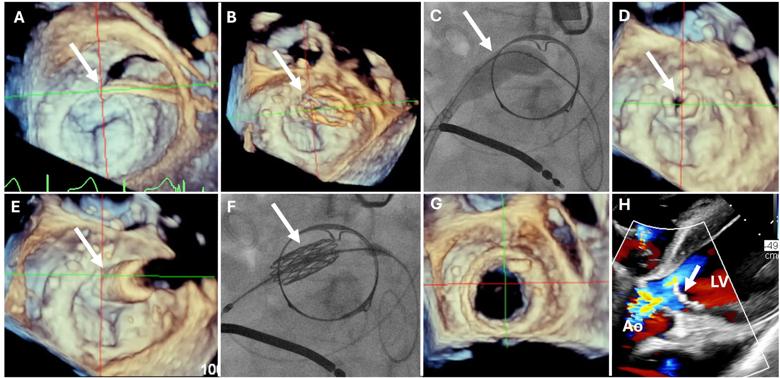

In 2023, Cleveland Clinic interventional cardiologists and imaging specialists reported a procedure they developed to mitigate LVOTO risk in this setting. The procedure, known as CLEVE (Cleveland Valve Electrosurgery), involves perforating the base of the anterior mitral valve leaflet and dilating it with a balloon to separate it from the prosthetic valve frame. When the transcatheter valve is inserted in the space, it pushes the entire surgical leaflet away, creating a larger opening and preventing LVOTO (Figure 2).

A recent review of Cleveland Clinic’s initial clinical experience with CLEVE (JACC Cardiovasc Interv. 2025;18[6]:767-781) confirmed complete clearance of the leaflet in 100% of cases.

Figure 2. Series of images showing the CLEVE procedure to facilitate MViV. (A) A catheter and wire (arrow) perforate the base of the surgical valve leaflet followed by inflation of a balloon in the leaflet (arrows in B and C) to separate the surgical leaflet from the valve frame (arrow in D). The valve is then positioned through the perforation (E and F) and deployed in place (G). Panel H shows post-placement flow from the left ventricle (LV) to the aorta (Ao) unimpeded by the surgical valve leaflet overhanging the open stent struts of the new valve (arrow).